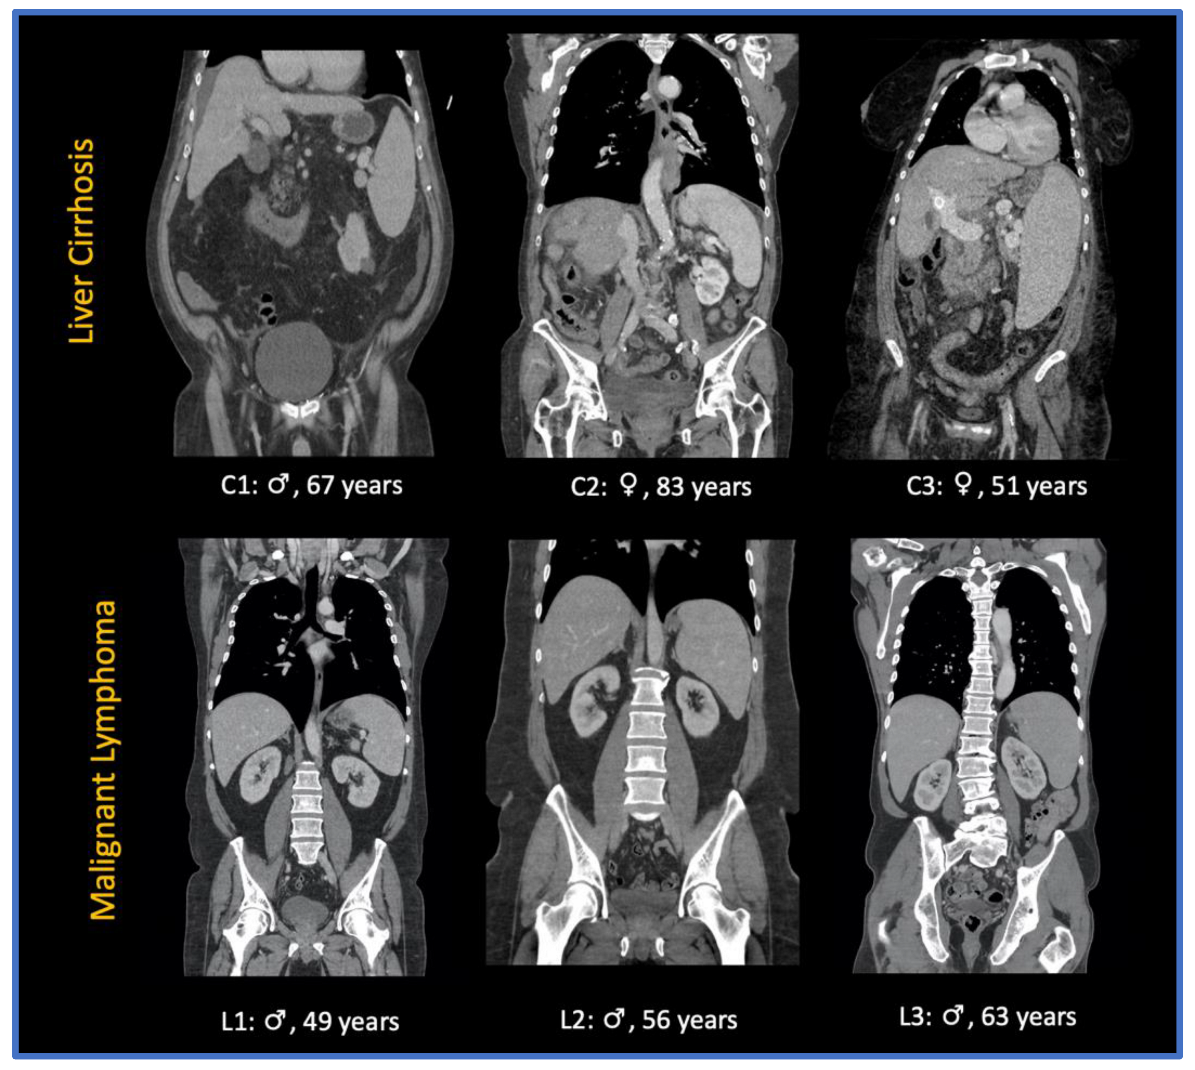

2.1. Study Population

2.2. CT Imaging Characteristics and Scanning Protocol

3.1. Study Population